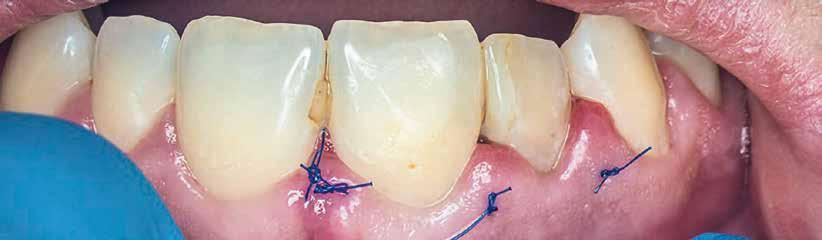

A gyökértömés elkészítése során meleg vertikális kompakciós technikát alkalmaztunk, sealerként pedig CeraSeal-t (Meta Biomed; 3. ábra) használtunk. A reszorbciós üreget Biodentine-nel (Septodont; 4. a–b ábra) töltöttük fel. A reszorbcióval érintett területtől koronális irányba elhelyezkedő csatornaszakaszt pedig tisztán meleg guttaperchával kezeltük. Ezt követően a lebenyszéleket visszafektettük, és varratok behelyezésével eredeti pozíciójuknak megfelelően rögzítettük. A koronai részt kompozit tömőanyag segítségével állítottuk helyre. Kontrollvizsgálatra 5, illetve 30 hónappal később került sor (5. ábra). A csontos telődés jelei már 5 hónap után észlelhetők voltak (6. a–c ábra). A 30 hónappal később végzett kontroll során sem találtunk csontban lévő lézióra, törésre vagy egyéb pathológiás elváltozásra utaló jeleket (7. a–b ábra)

9. a–b ábra: A műtét előtt (a) és a lebeny felemelését követően látható állapot (b). – 10. a–d ábra: A granulációs szövet eltávolítása.

13. a–c ábra: A reszorbtív üreg bioanyaggal való feltöltése és a kollagénszivacs elhelyezése. – 14. a–b ábra: Posztoperatív röntgen (a), a varratok behelyezését követően látható klinikai helyzet (b).